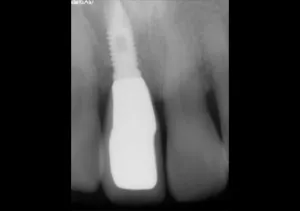

症例③

| 主訴 | 他院にて抜歯後、歯を入れたい |

|---|---|

| 診断名 | 歯根破折 |

| 年齢 | 46歳 |

治療に用いた装置(治療法) | 骨造成・インプラント |

| 部位 | 右上1 |

| 治療期間 | 8か月 |

| 治療費用 | 造成:55,000円 インプラント:462,000円 |

| リスク・副作用(治療に関する) | 腫服、しびれ |